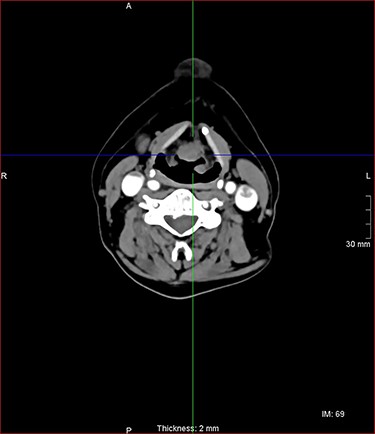

A laryngeal abnormality was noted, and he was referred to ENT for further assessment (Fig. 1). Flexible nasendoscopy showed a lesion on the laryngeal surface of the epiglottis in the midline. Vocal cords were not affected, although the lesion was extending close to the anterior commissure. An 18 × 14-mm lesion was found on magnetic resonance imaging (MRI) at the right paracentral supraglottic region, crossing the midline with possible involvement of the base of epiglottis (Fig. 2). There was no destruction of the thyroid cartilage or hyoid bone, and no involvement of the para-epiglottic space or glottis. There were no pathological cervical lymph nodes. Further CT scanning of the neck and chest confirmed the above, with no lung metastases identified (Figs 3 and 4).

axial postcontrast CT images of the neck with similar lesion related to the base of epiglottis, no involvement of the pre epiglottic fat.